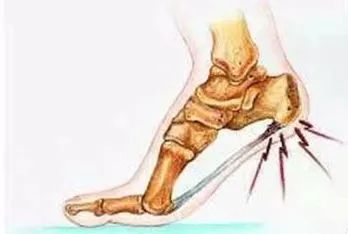

跖筋膜炎:本病因长期的职业关系站立在硬地面工作,或因扁平足,使跖腱膜长期处于紧张状态,在其起点处因反复牵拉发生充血、渗出,日久则骨质增生,形成骨刺。

鞋子、外伤、长期站立、肥胖、肾虚等造成足跟关节磨损、破坏,人体自身会进行自我的修复,硬化与增生,从而形成足跟骨刺。